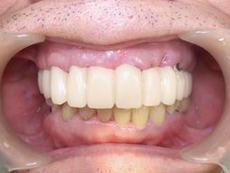

3回目の仮歯です。ゴールが見えてきましたが左上前歯2本の深い傷があります。